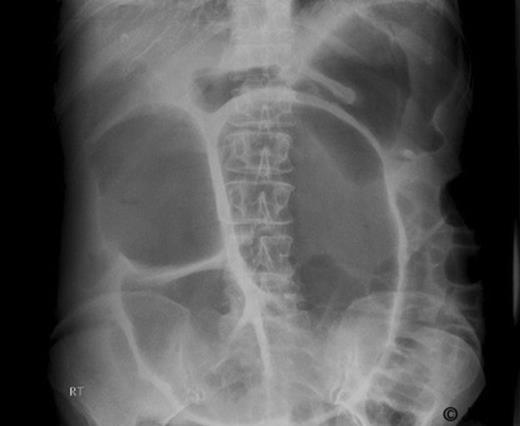

Subsequently, in March 2007, the patient developed weight loss and abdominal pain. CT revealed liver metastasis and local relapse at the splenic flexure. She was commenced on second line chemotherapy. She later presented to the emergency department in August 2007 with abdominal pain and marked abdominal distension. Physical examination revealed abdominal distension with no features of peritonism or intestinal obstruction. Abdominal X-Ray revealed distended bowel loops (Figure 1). She was initially managed conservatively. Due to lack of clinical improvement, it was decided to proceed to laparotomy for large bowel obstruction.